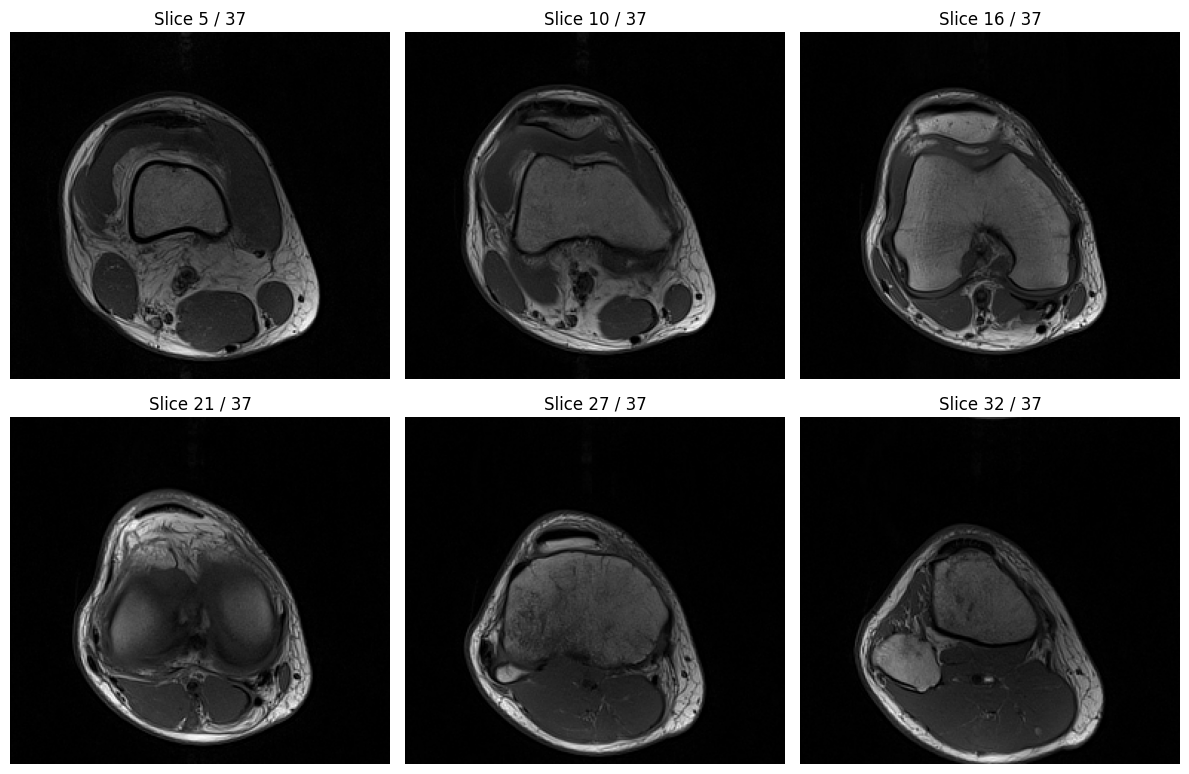

import matplotlib.pyplot as plt

# Visualize a few representative slices from the volume

fig, axes = plt.subplots(2, 3, figsize=(12, 8))

axes = axes.flatten()

# Select 6 evenly spaced slices to display

num_slices = volume.shape[0]

slice_indices = [int(i * num_slices / 7) for i in range(1, 7)]

for idx, ax in enumerate(axes):

slice_idx = slice_indices[idx]

ax.imshow(volume[slice_idx], cmap="gray")

ax.set_title(f"Slice {slice_idx} / {num_slices-1}")

ax.axis("off")

plt.tight_layout()

plt.show()